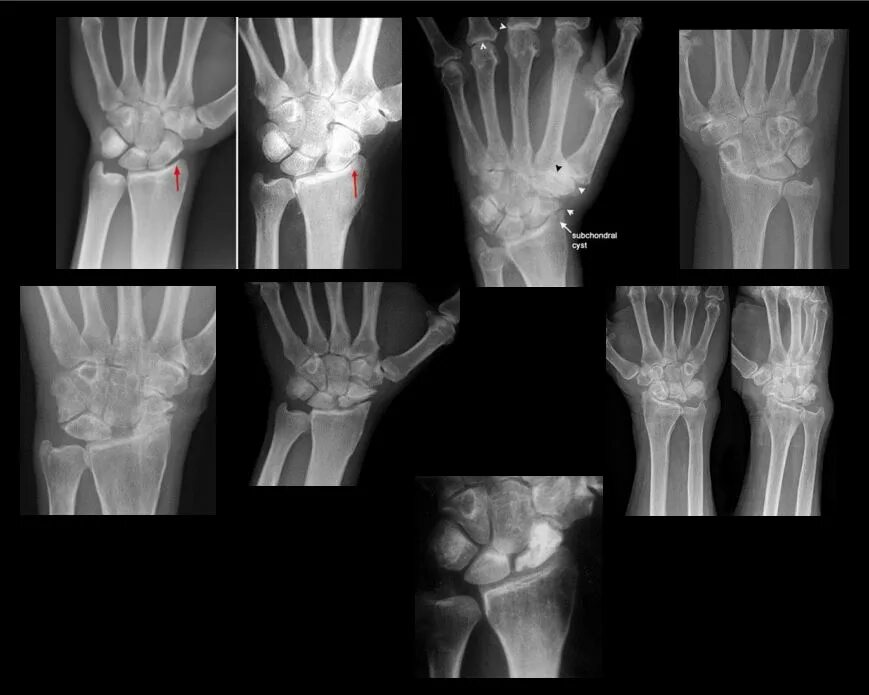

Ушиб лучезапястного